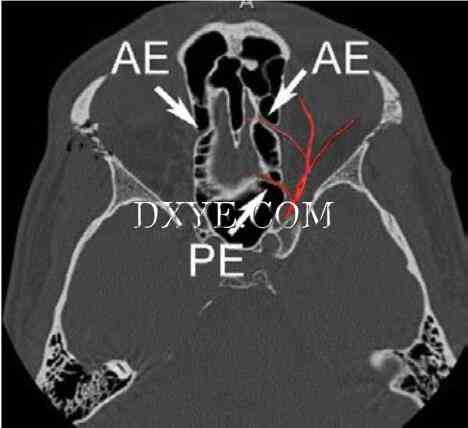

图. 2.6 急性右眶骨折患者嗅隐窝水平轴位像。 筛前动脉管(AE)显示双侧。 左侧眼动脉分支的叠加示意图还显示后方行走的筛后动脉(PE)。